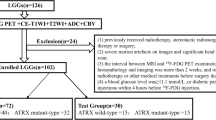

A total of 111 LrGG patients (76 mutated IDH and 35 wild-type IDH) were enrolled, divided into a training set (n = 78) and a validation set (n = 33) for predicting IDH mutation. IDH + LrGG patients were further stratified into the ATRX − (n = 38) and ATRX + (n = 38) subtypes. A total of 250 radiomics features were extracted from the region of interest of each tumor, including that from T2 fluid-attenuated inversion recovery (T2 FLAIR), contrast-enhanced T1 WI, ASL-derived cerebral blood flow (CBF), DWI-derived ADC, and exponential ADC (eADC). A radiomics signature was selected using the Elastic Net regression model, and a radiomics nomogram was finally constructed using the age, gender information, and above features.